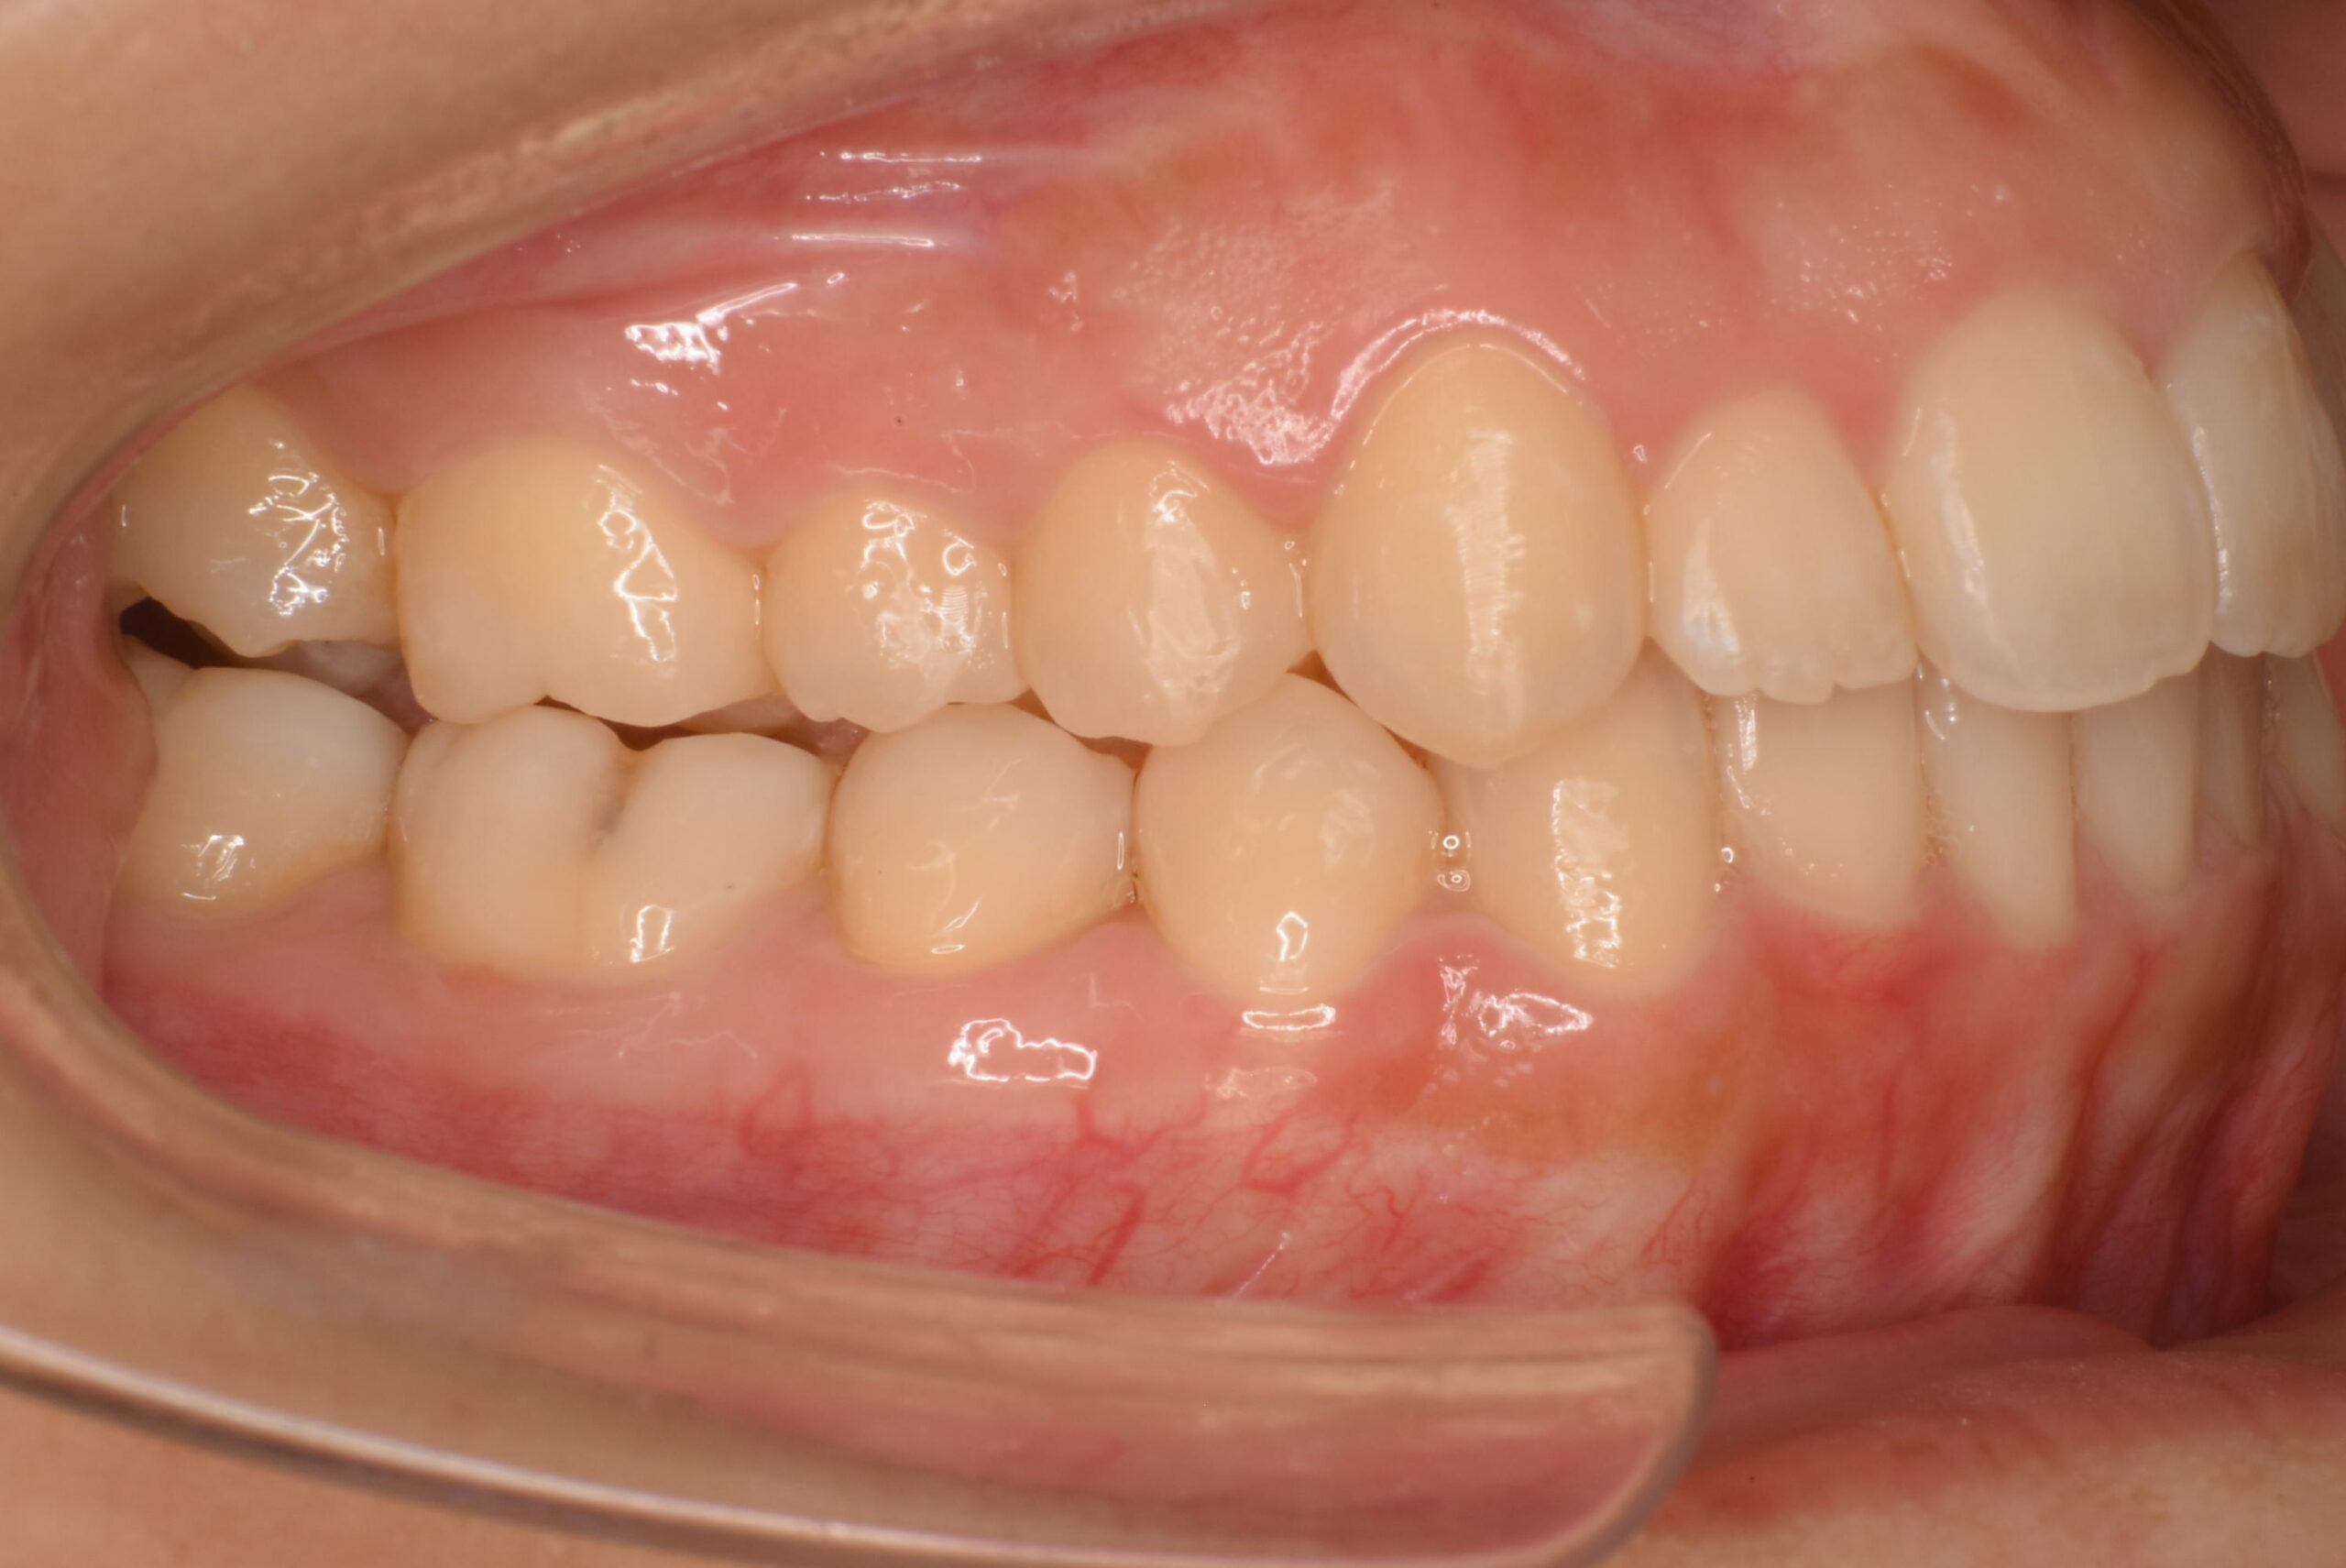

治療後_右側方

| 治療内容 | 患者様は、歯のガタつきやデコボコした不揃いな歯並び、歯に汚れがつきやすく磨きにくいことを主訴に来院されました。10年以上ぶりの歯科受診で、歯ぐきからの出血(歯肉炎:歯肉病の初期症状)が多く見られたため、インビザライン治療に入る前にブラッシング指導(TBI)や歯周病治療を行い、口腔内環境を整えてから矯正治療を開始しました。 治療開始前には左上の歯の虫歯治療を行い、その後インビザライン治療をスタートしました。抜歯は行わず、非抜歯矯正で歯列を整える方針とし、歯の移動に必要なスペースを確保するために IPR を行いながら治療を進めました。インビザライン治療と並行して歯周病治療も継続し、歯列の改善と口腔内の健康維持の両方を図りました。 |

| 治療期間/通院回数 | 19ヶ月 |